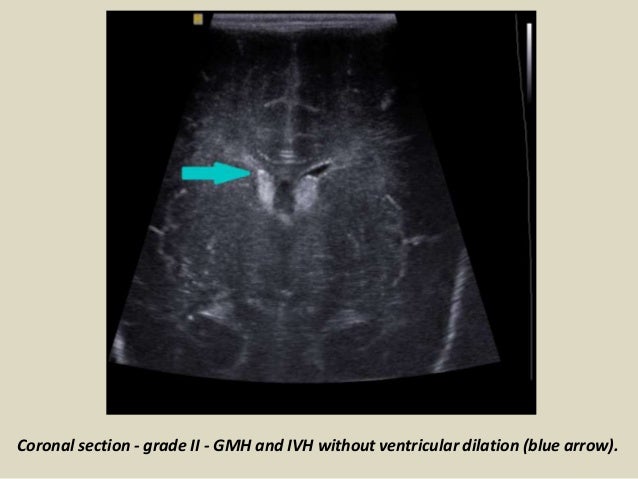

17. 17. Coronal section - grade II - GMH and IVH without ventricular dilation (blue arrow).

18. 18. LEFT: Coronal image, green arrow indicating grade 3 hemorrhage RIGHT: Sagittal image, yellow arrow indicating venous infarction.